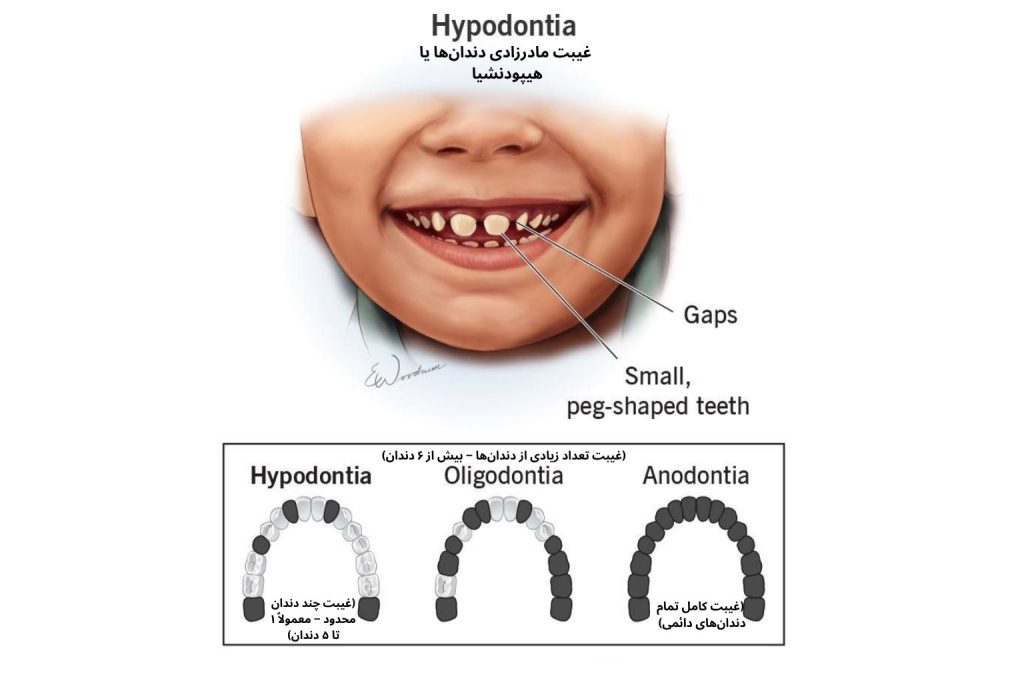

غیبت مادرزادی دندان ها یکی از ناهنجاریهای تکاملی نسبتاً شایع در دستگاه دهان است که در آن، یک یا چند دندان از ابتدا تشکیل نمیشوند و جوانه دندانی آنها هرگز بهوجود نمیآید. این پدیده معمولاً بهصورت تصادفی و در دندانهای خاصی از قوس دندانی رخ میدهد، اما در برخی موارد میتواند گستردهتر باشد. هنگامی که تنها یک یا چند دندان غایب باشند، این وضعیت را هیپودنشیا (Hypodontia) مینامند و اگر هیچیک از دندانهای دائمی تشکیل نشوند، به آن ادنتیا (Anodontia) گفته میشود.

از دیدگاه زیبایی نیز، غیبت دندانی — بهویژه در نواحی قدامی — سبب برهم خوردن هماهنگی لبخند میشود. در غیبت دندانهای جلویی یا لترال، فاصلهای ناهمگون در لبخند دیده میشود که علاوه بر تأثیر ظاهری، میتواند بر اعتماد بهنفس و احساس رضایت فرد از ظاهر خود اثر منفی بگذارد.

- دندانهای لترال ماگزیلا (کناری جلوی فک بالا): یکی از شایعترین دندانهای غایب مادرزادی که نبودشان باعث مشکلات زیبایی آشکار میشود.